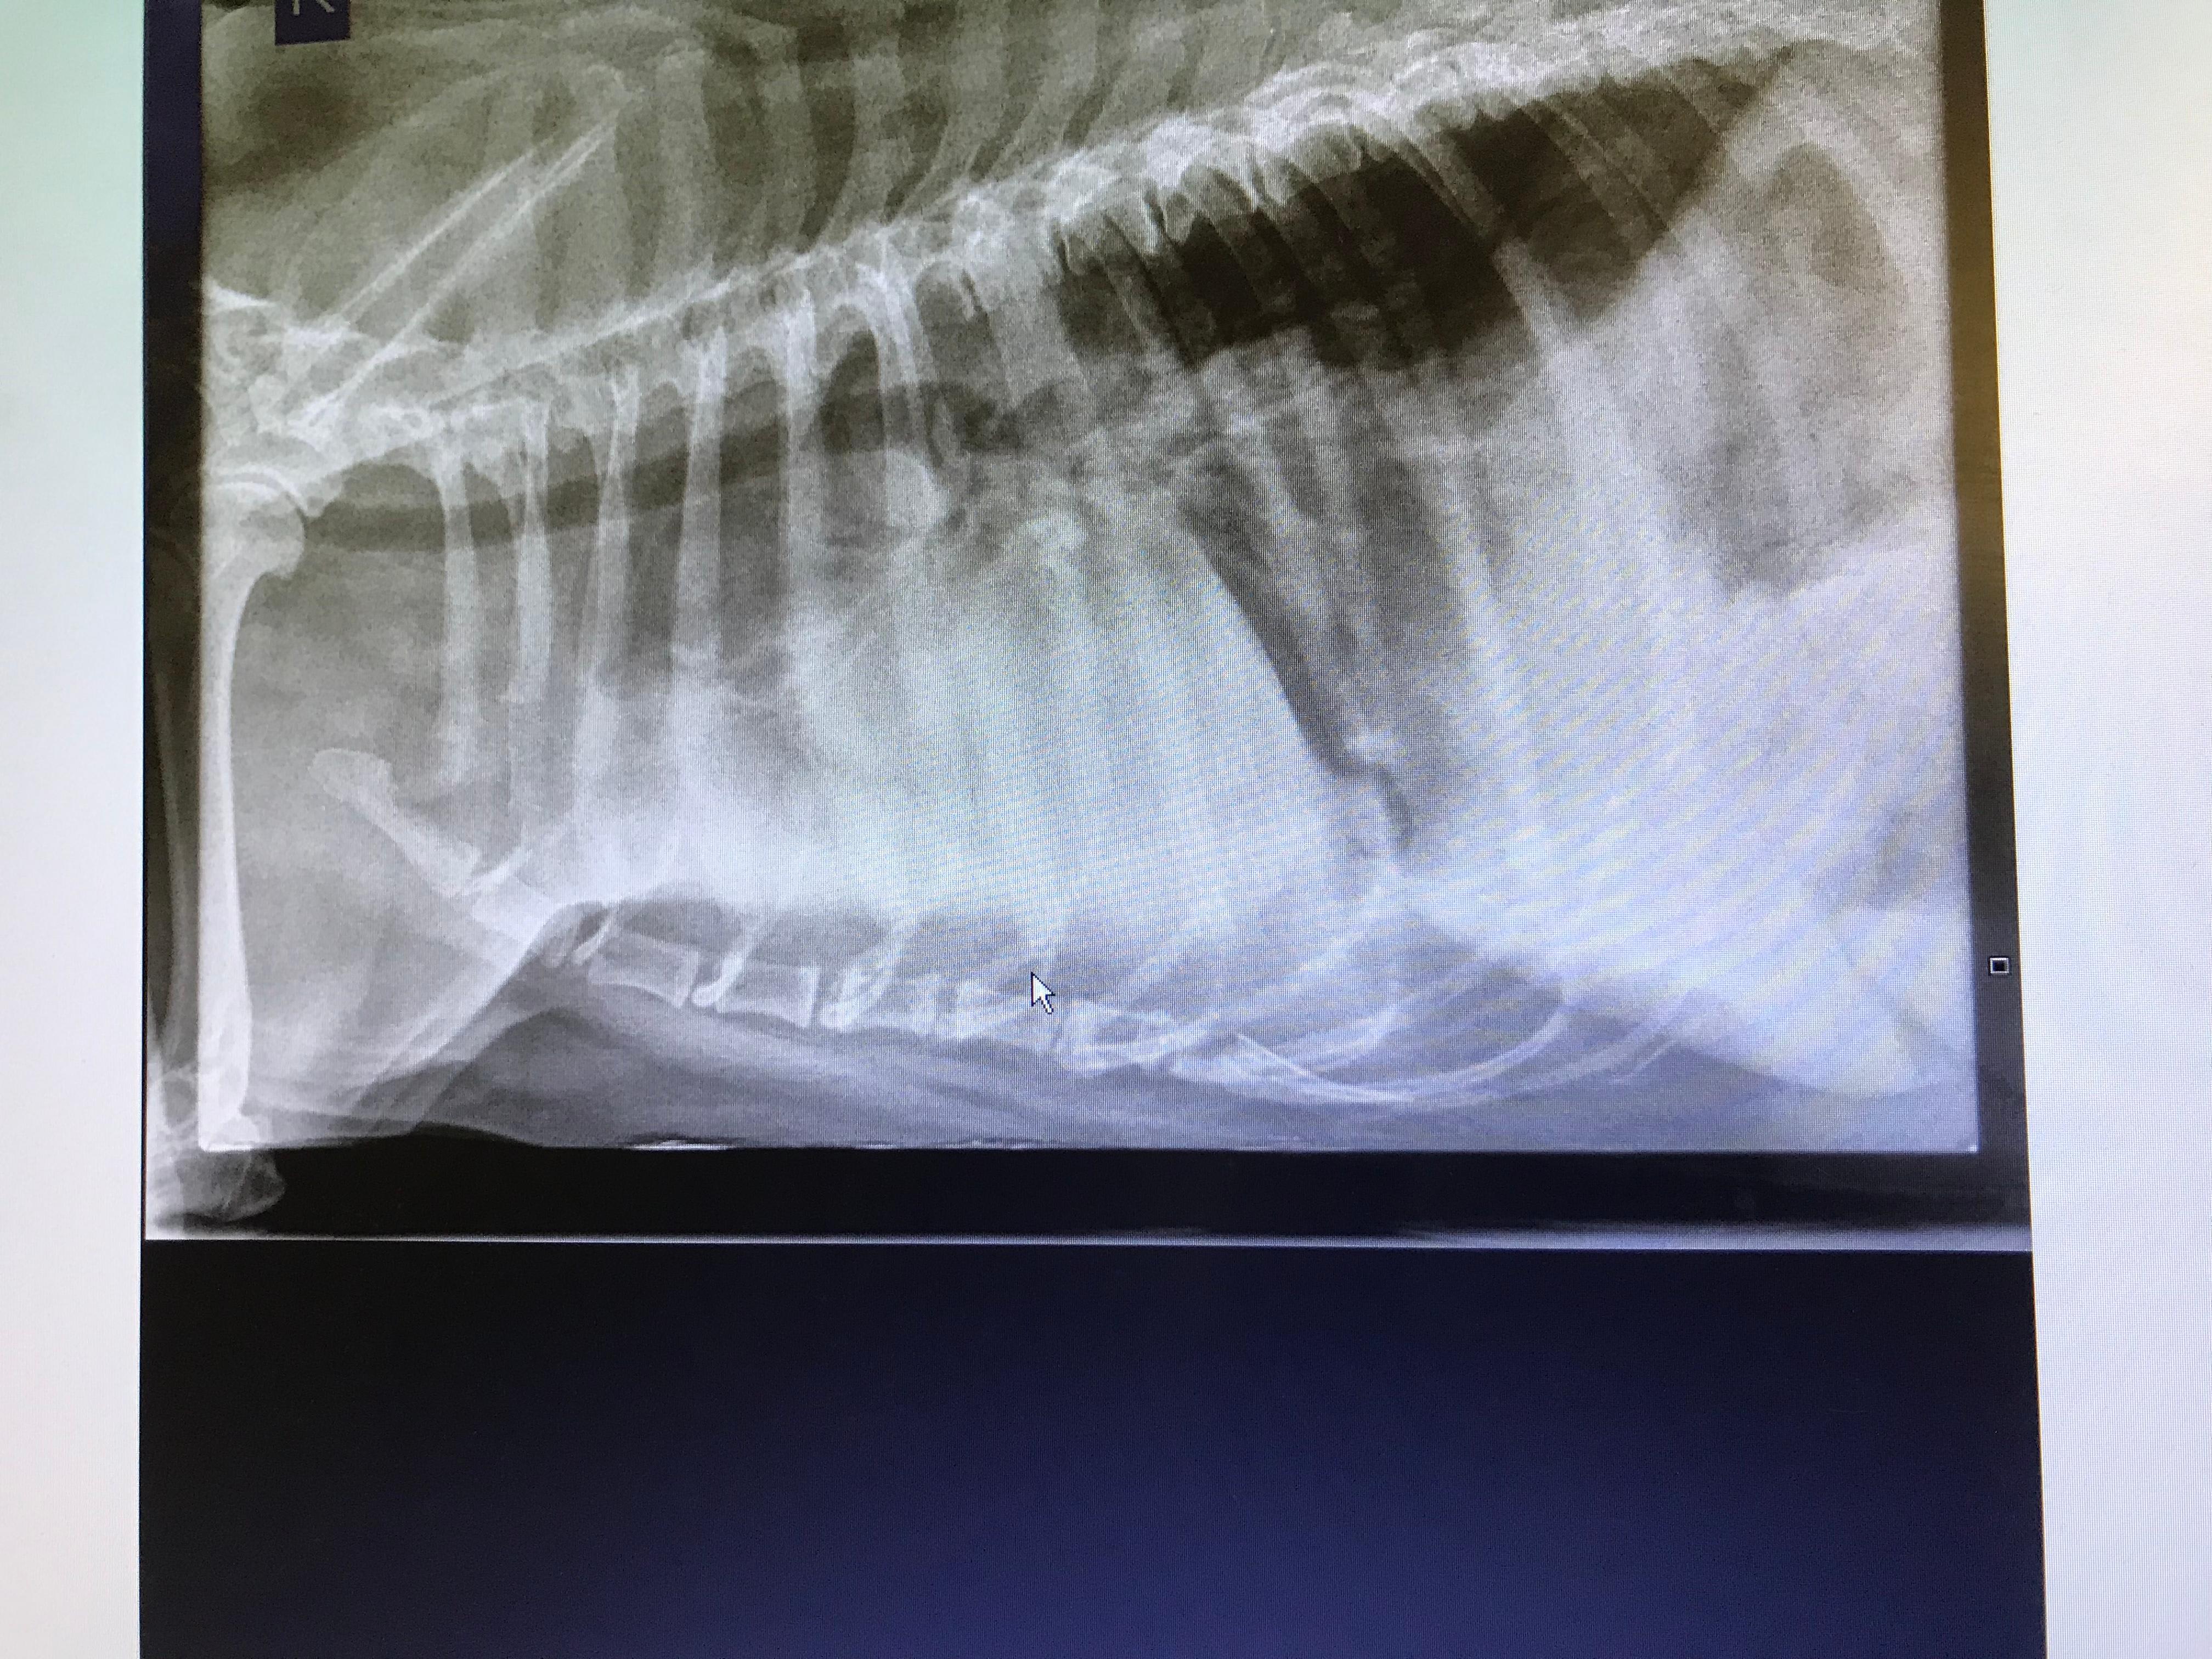

My dog's X-ray shows lung issues. How to tell pneumonia from cancer?

Hi, I’d really appreciate some clarity on some x rays given to me by my vet, she is unable to tell me whether this is pneumonia or lung cancer in my 7 year old rescue Rottweiler Edie Thanks

An X-ray shows abnormalities like those Edie has in her lungs. They do not give a diagnosis. More tests need to be done to determine if this is pneumonia or cancer. They will look at the white blood cell count for infection and they can do cytology on the bronchial discharge to see if it’s infection or if cancer cells are present. If you want you can take Edie to a specialist to complete the additional tests needed to get a definitive diagnosis. Once there is a diagnosis then they can treat her appropriately. Thanks for using Petco Pet Education Center, formerly Petcoach to help you care for Edie.